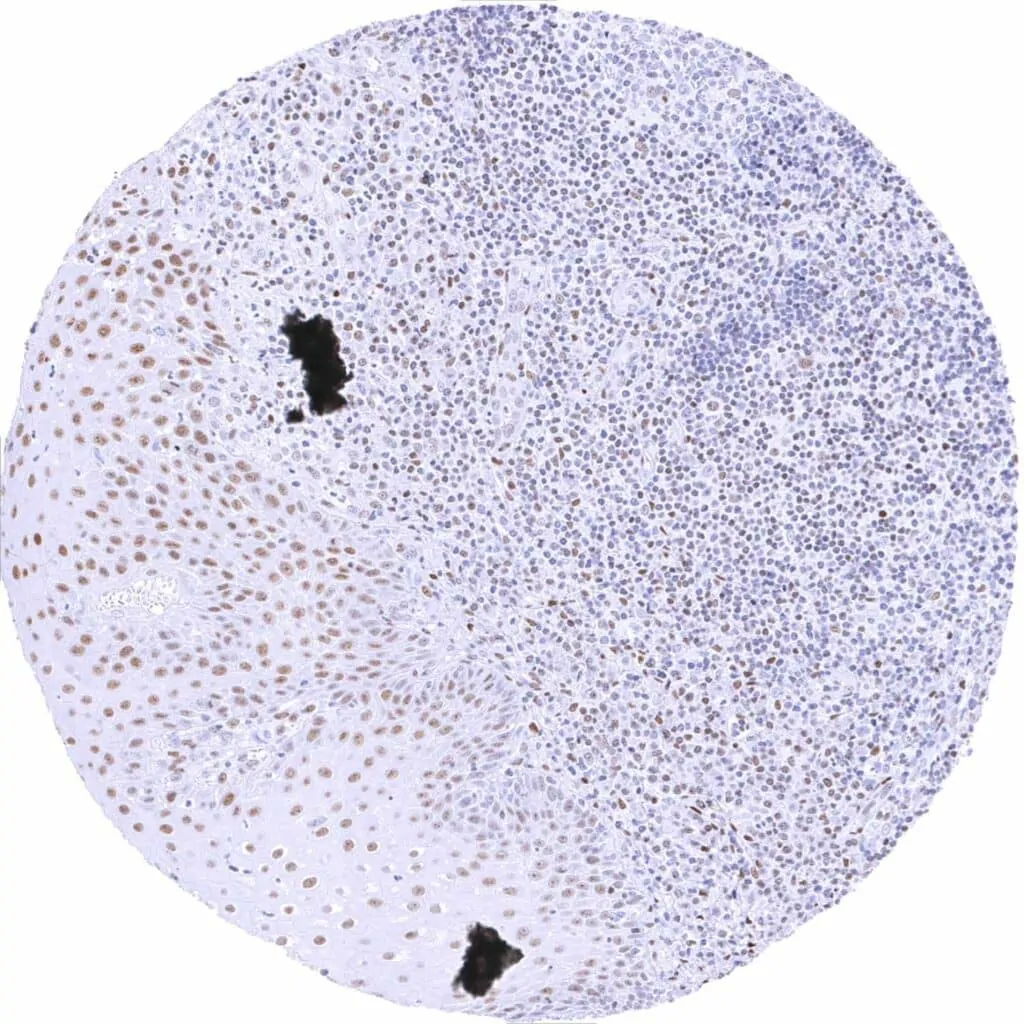

Testis – Moderate to strong TLE1 staining of spermatogonia